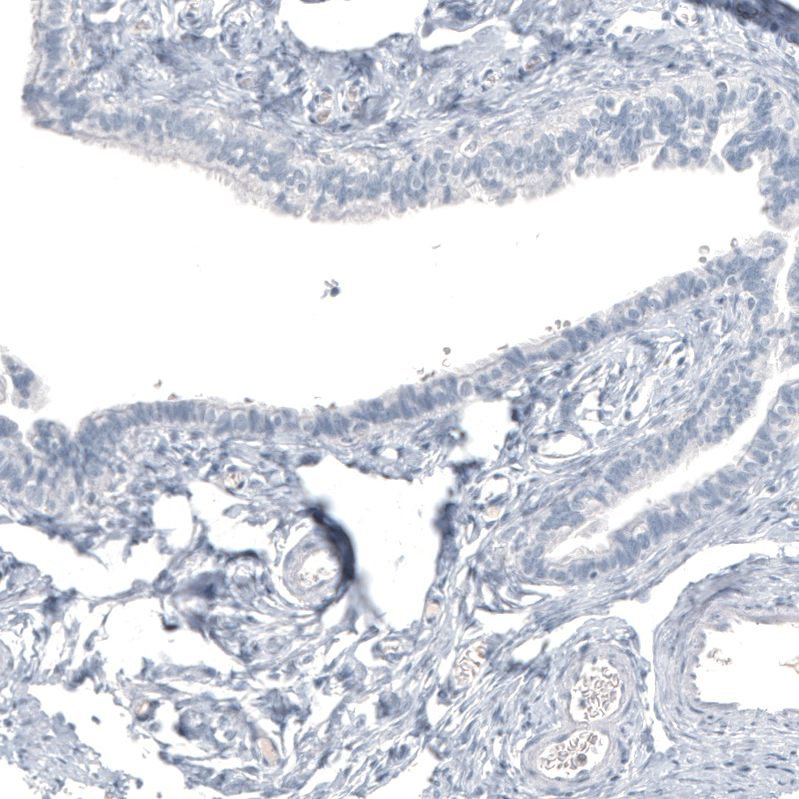

Immunohistochemistry analysis in human spleen and skeletal muscle tissues using AMAb91719 antibody. Corresponding HMOX1 RNA-seq data are presented for the same tissues.